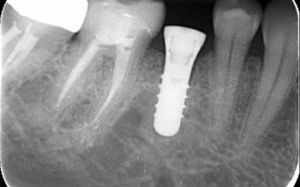

About implant dentistry

Most cases it is a single surgical procedure where the periodontist will place the implant in your jawbone and a healing cap above the gum line. After 3 month the periodontist will review the implant for the final stage of treatment. There are some circumstances where the implant will stay under the gum for 3-6 month while it hardens in the bone.

The next step is for the periodontist to uncover the implant from the gum and put a neck on the implant. You will then come back to Kissing Point Dental to have a crown attach to the implant.